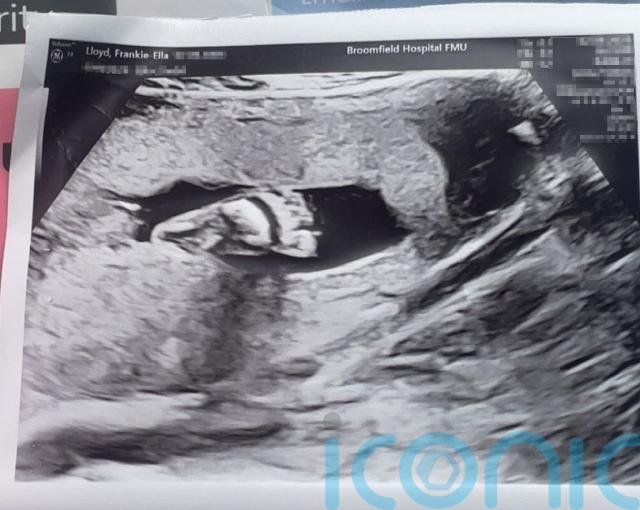

Frankie-Ella said she was in “shock” and “disbelief”, and she took 16 at-home pregnancy tests to be sure before booking an ultrasound scan that confirmed the news.

Frankie-Ella is now 35 weeks along in her pregnancy and in a letter seen by PA Real Life, her doctor described the situation as “a medical miracle”.

She and her baby are now being monitored with scans twice a week in the run-up to her due date in early January.